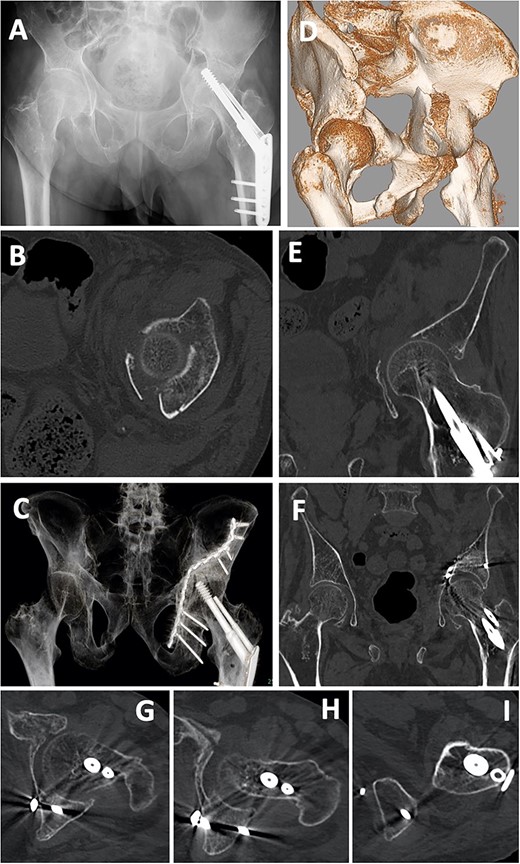

A 66-year-old man, who walked with a stick, was injured in a fall during a sudden convulsion. He could not move his left lower extremity due to pain and rested in his house. After 3 days, he developed a fever (>38°C) and was admitted to a nearby hospital. Diagnostic imaging showed a quadrilateral fracture (Fig. 7A, B, D, E). Twelve days after injury, open reduction and internal fixation for the acetabular fracture were performed using a low-profile pelvic plate system by the classical ilioinguinal approach, as in case 1. After a 13-hole reconstruction plate was bent and placed at the quadrilateral surface, screws were inserted to the posterior column and ischium using the sleeve guide technique (Fig. 7C, F–I). Six weeks after the operation, partial weight-bearing was started. After 3 months, he was able to walk with a rollator, and after 1 year, he walked with a stick.

Case 2 images: (A) pre-operative X-ray, (B) pre-operative axial CT image, (C) post-operative X-ray, (D) pre-operative 3D-CT, (E) pre-operative coronal CT image, (F) post-operative 3D-CT, (G–I) post-operative axial CT images. Screws are inserted into the posterior wall (G, H) and near the ischial tuberosity (I).